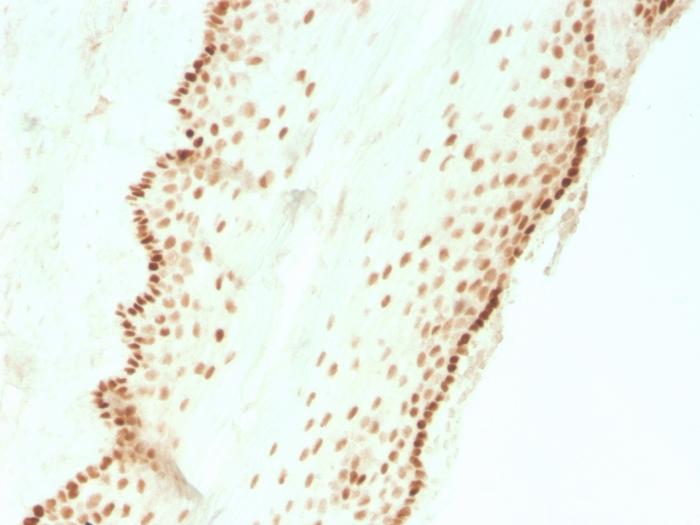

SOX2 (Embryonic Stem Cell Marker)(SOX2/3811R), 0.2mg/mL

SOX2 is required for stem cell maintenance in the central nervous system, and it also regulates gene expression in the stomach. SOX2 is necessary for regulating multiple transcription factors that affect Oct 3/4 expression. An essential function of SOX2 is to stabilize embryonic stem cells in a pluripotent state by maintaining the requisite level of Oct 3/4 expression. Reportedly, SOX2 is associated with aggressive phenotypes of breast, head and neck, gastric, colorectal, bladder, and small cell lung cancers. However, SOX2 is expressed in a high percentage of lung squamous cell carcinomas and has been shown to be an independent favorable prognostic marker. Primary antibodies are available purified, or with a selection of fluorescent CF® Dyes and other labels. CF® Dyes offer exceptional brightness and photostability. Note: Conjugates of blue fluorescent dyes like CF®405S and CF®405M are not recommended for detecting low abundance targets, because blue dyes have lower fluorescence and can give higher non-specific background than other dye colors.

Positive Control

Antibody target cellular localization

Nucleus

IHC, FFPE (verified)